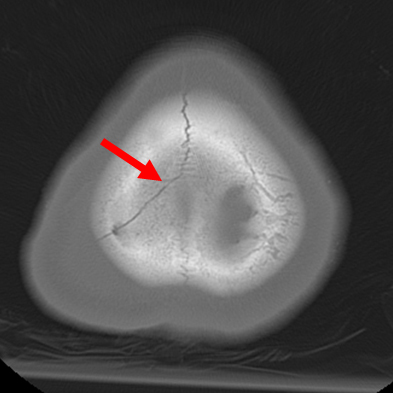

Screening for Wilson's disease should be considered in patients with abrupt-onset psychosis. Intial tests include ceruloplasmin, 24-hour urine copper excretion, and a slit-lamp ophthalmological examination to detect Kayser-Fleischer rings. Other tests include total serum copper, liver biopsy, and genetic investigation of ATP7B.[62]

[Figure caption and citation for the preceding image starts]: Eye demonstrating Kayser-Fleischer ringAdapted from BMJ (2009), used with permission; copyright 2009 by the BMJ Publishing Group [Citation ends].